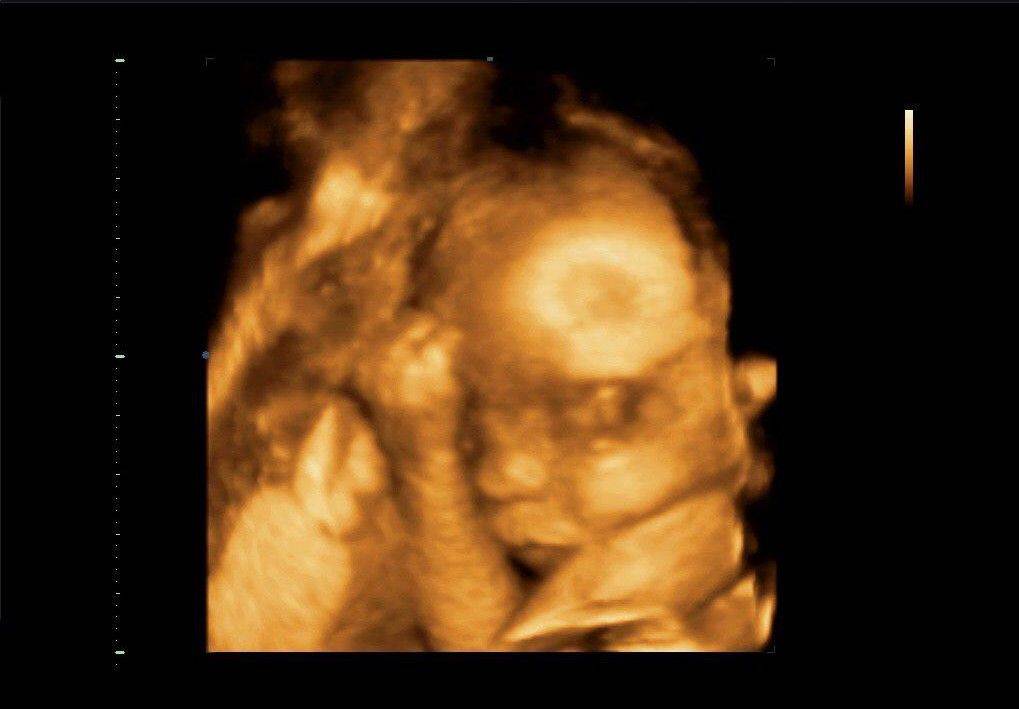

3D УЗИ – это вид эхографии, при котором трёхмерная объёмная картинка формируется из двухмерных изображений. Сканирование позволяет определить пол малыша, рассмотреть его лицо и даже пальчики на руках и ногах. По сравнению с обычным двухмерным УЗИ никаких сверхвозможностей 3D-сканирование не даёт. Это не замена, а, скорее, дополнение к плановому сканированию. Но иногда объёмная картинка даёт возможность лучше рассмотреть некоторые детали. Например, на картинке можно увидеть, что лицо ребёнка сморщено. А это свидетельствует о кислородном голодании.

На фотографии, результатом которой будет проведённое 3D УЗИ, можно отчётливо увидеть черты лица младенца, его пальчики на ручках и ножках, после чего даже поспорить с супругом о том, на кого же он уже похож, несмотря на то, что ещё находится в утробе. Многие родители уже оценили этот вид исследования и к рождению ребёнка даже имеют небольшой фотоальбом с ним.